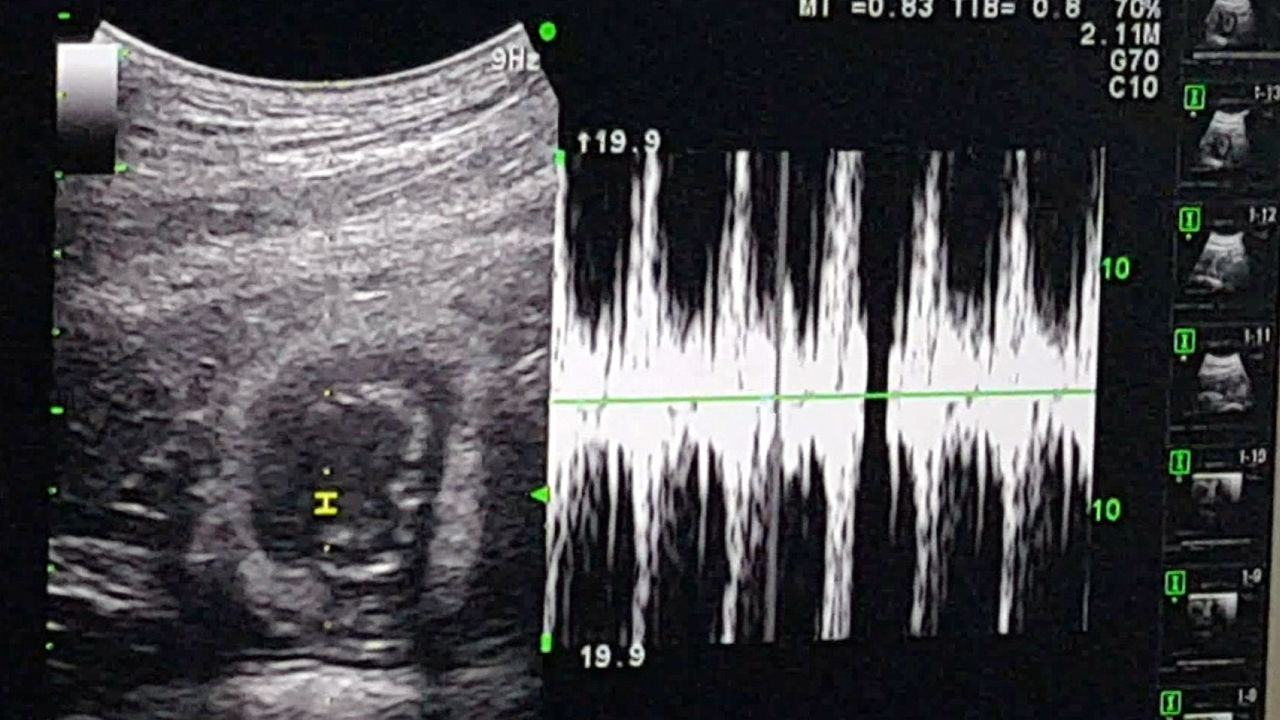

연구팀은 새끼 반달곰으로부터 혈액과 모근을 채취해 유전자 분석에 들어갔고, 최근 새끼 3마리 가운데 2마리가 인공수정을 통해 태어난 개체임을 확인했다. 이 새끼 반달곰의 유전자가 정자를 제공한 아빠곰 RM-19의 유전자와 일치한 것으로 나타났다. CF-38이 낳은 2마리 중 1마리는 인공수정이 아닌 증식장에서 자연교미를 통해 태어난 개체로 확인됐다. 한 엄마 몸에서 아빠가 서로 다른 반달곰이 태어난 것이다. 앞서 연구팀은 지난해 12월 초음파영상을 통해 어미곰 2마리의 임신을 확인했다.